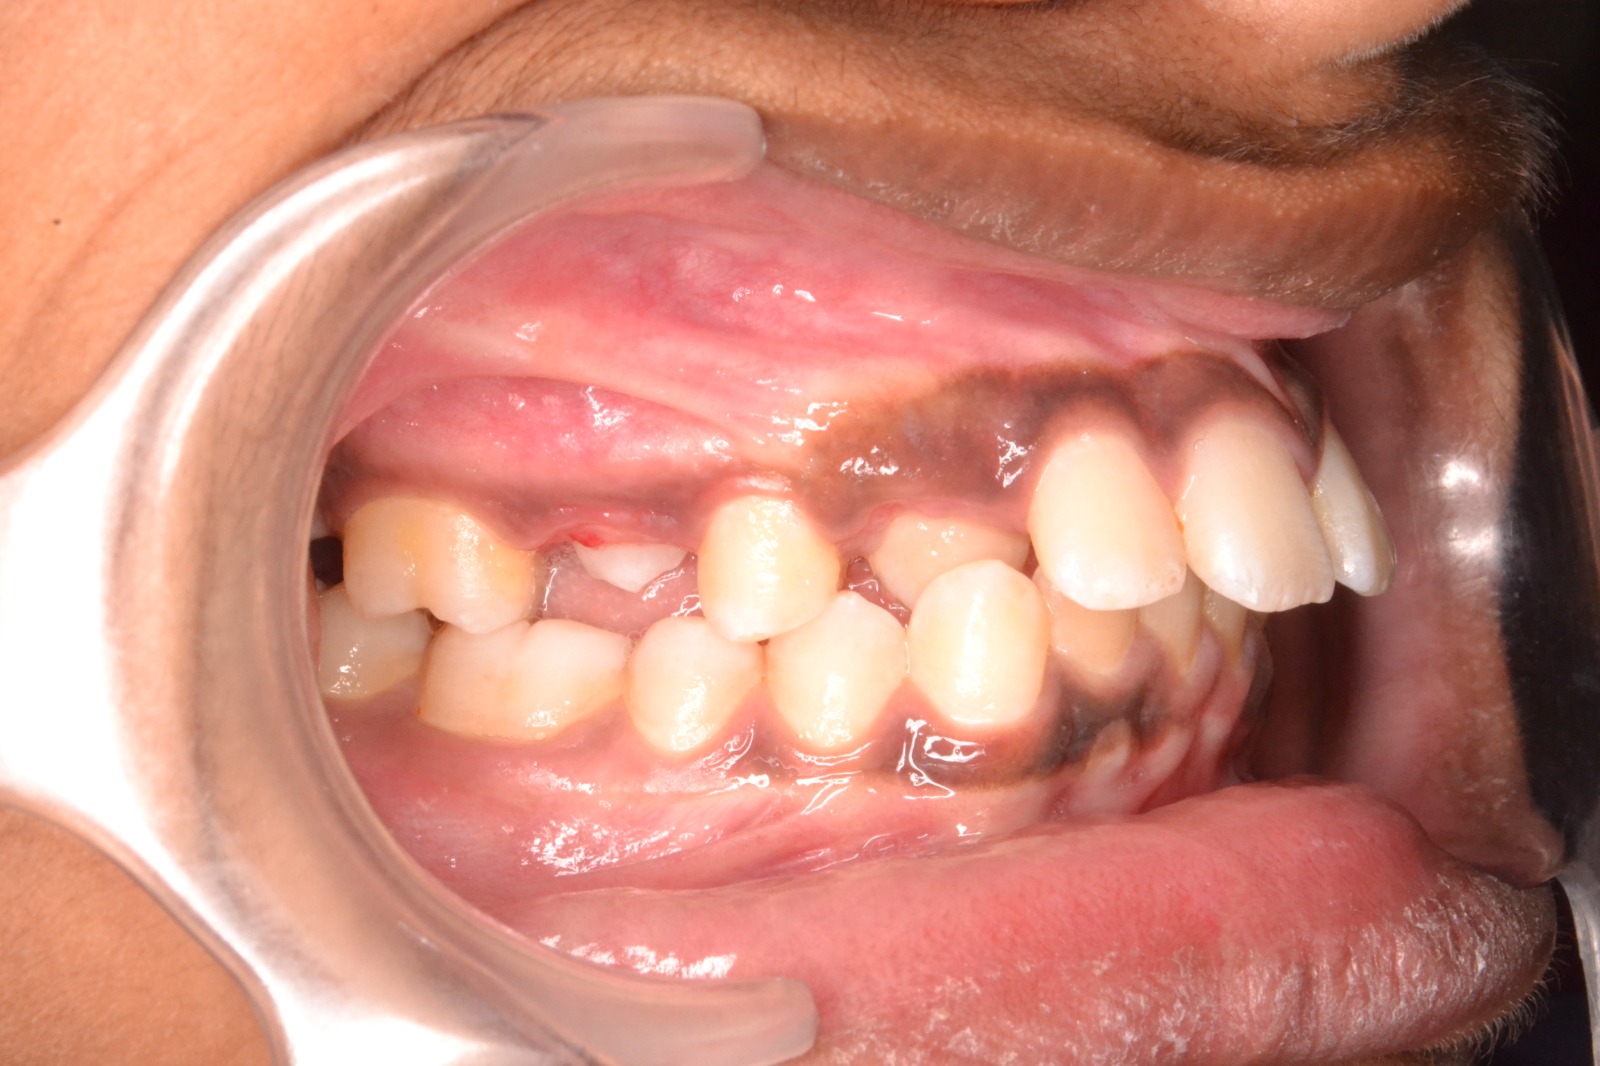

After/Before

See stunning smile transformation before and after

Before After